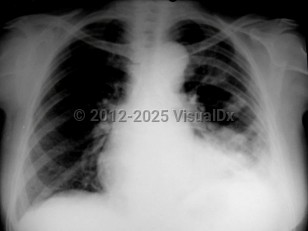

On migration of flukes into the lungs, patients can experience fevers, cough productive of brownish sputum, and occasionally hemoptysis as early signs of chronic pulmonary infection. Profuse expectoration, pleuritic chest pain, dyspnea, chronic cough, and intermittent hemoptysis collectively comprise symptoms of chronic pleuropulmonary paragonimiasis (typically 6 months after exposure).